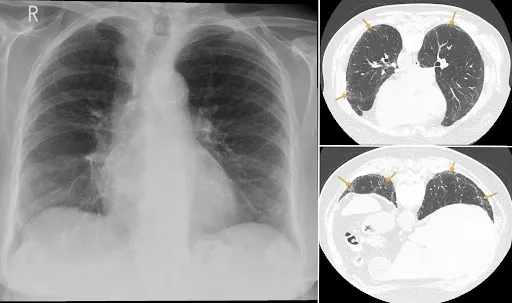

A lung CT scan of idiopathic pulmonary fibrosis (IPF)